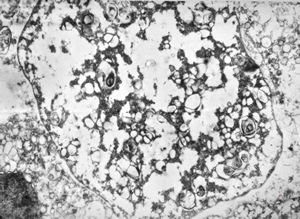

M,54y. | Whipple disease

Whipple disease